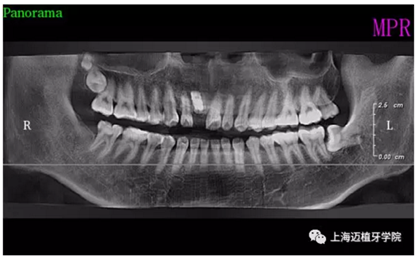

術(shù)前全景片

主訴:前門外傷牙根折要求修復(fù)?現(xiàn)病史:前門牙外傷,劈裂至根部,無法固定及其他修復(fù),要求種植?檢查:11牙冠2/3缺損,唇腭向劈裂,唇部紅腫。 CT示根折, 骨寬度9.47mm,距鼻底12.34mm,Ⅲ類骨。 口腔衛(wèi)生一般